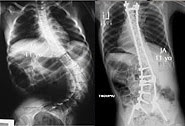

![]() |

| Fuente: Illinois Spine & Soliosis Center |